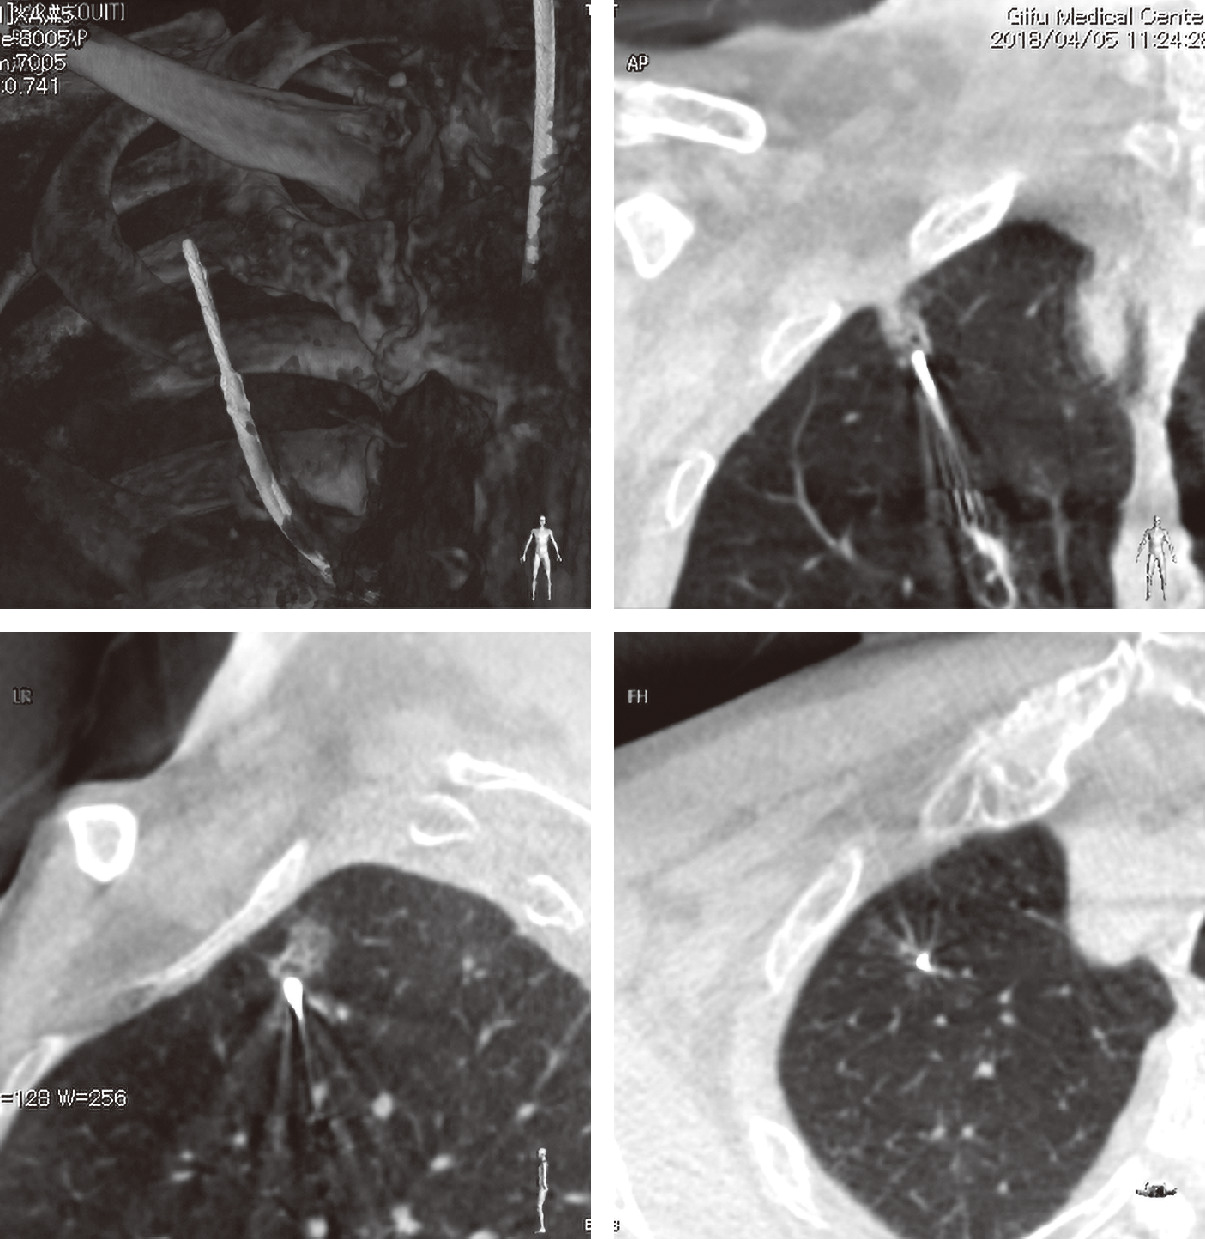

カラー ルービン病理学: 臨床医学への基盤 | ラファエル。新品未使用】カラー ルービン病理学 臨床医学への基盤 改訂版。カラー ルービン病理学: 臨床医学への基盤 | ラファエル。p*す様 ミルキークイーン ☆ 玄米 ☆ 10kg。カラー ルービン病理学: 臨床医学への基盤 | ラファエル。病理学 - 西村書店。朝倉書店『内科学』(第12版)デジタル付録。「カラー ルービン病理学 臨床医学への基盤」鈴木 利光 / 中村 栄男 / エマニュエル・ルービン定価: ¥ 11000#鈴木利光 #鈴木_利光 #中村栄男 #中村_栄男 #エマニュエル・ルービン #本 #自然/医療・薬学・健康。ルービンカラー基本病理学 第5版 | エマニュエル ルービン。カラー ルービン病理学: 臨床医学への基盤 | ラファエル。ルービン カラー 調和のとれた 基本病理学 中古本。国内初、先天性中枢性低換気症候群に対する横隔膜ペーシング治療。脳血管の分子病態研究 | 研究紹介 - 新潟大学脳研究所 脳神経内科。日本がん対策図鑑 | 【標準治療】EGFR陽性肺がん